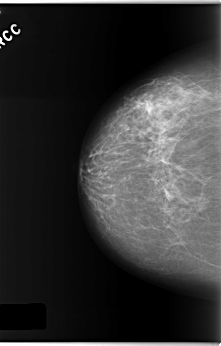

C_0173_1.RIGHT_CC

RIGHT_CC LINES 5872 PIXELS_PER_LINE 3752 BITS_PER_PIXEL 12 RESOLUTION 50 NON_OVERLAY